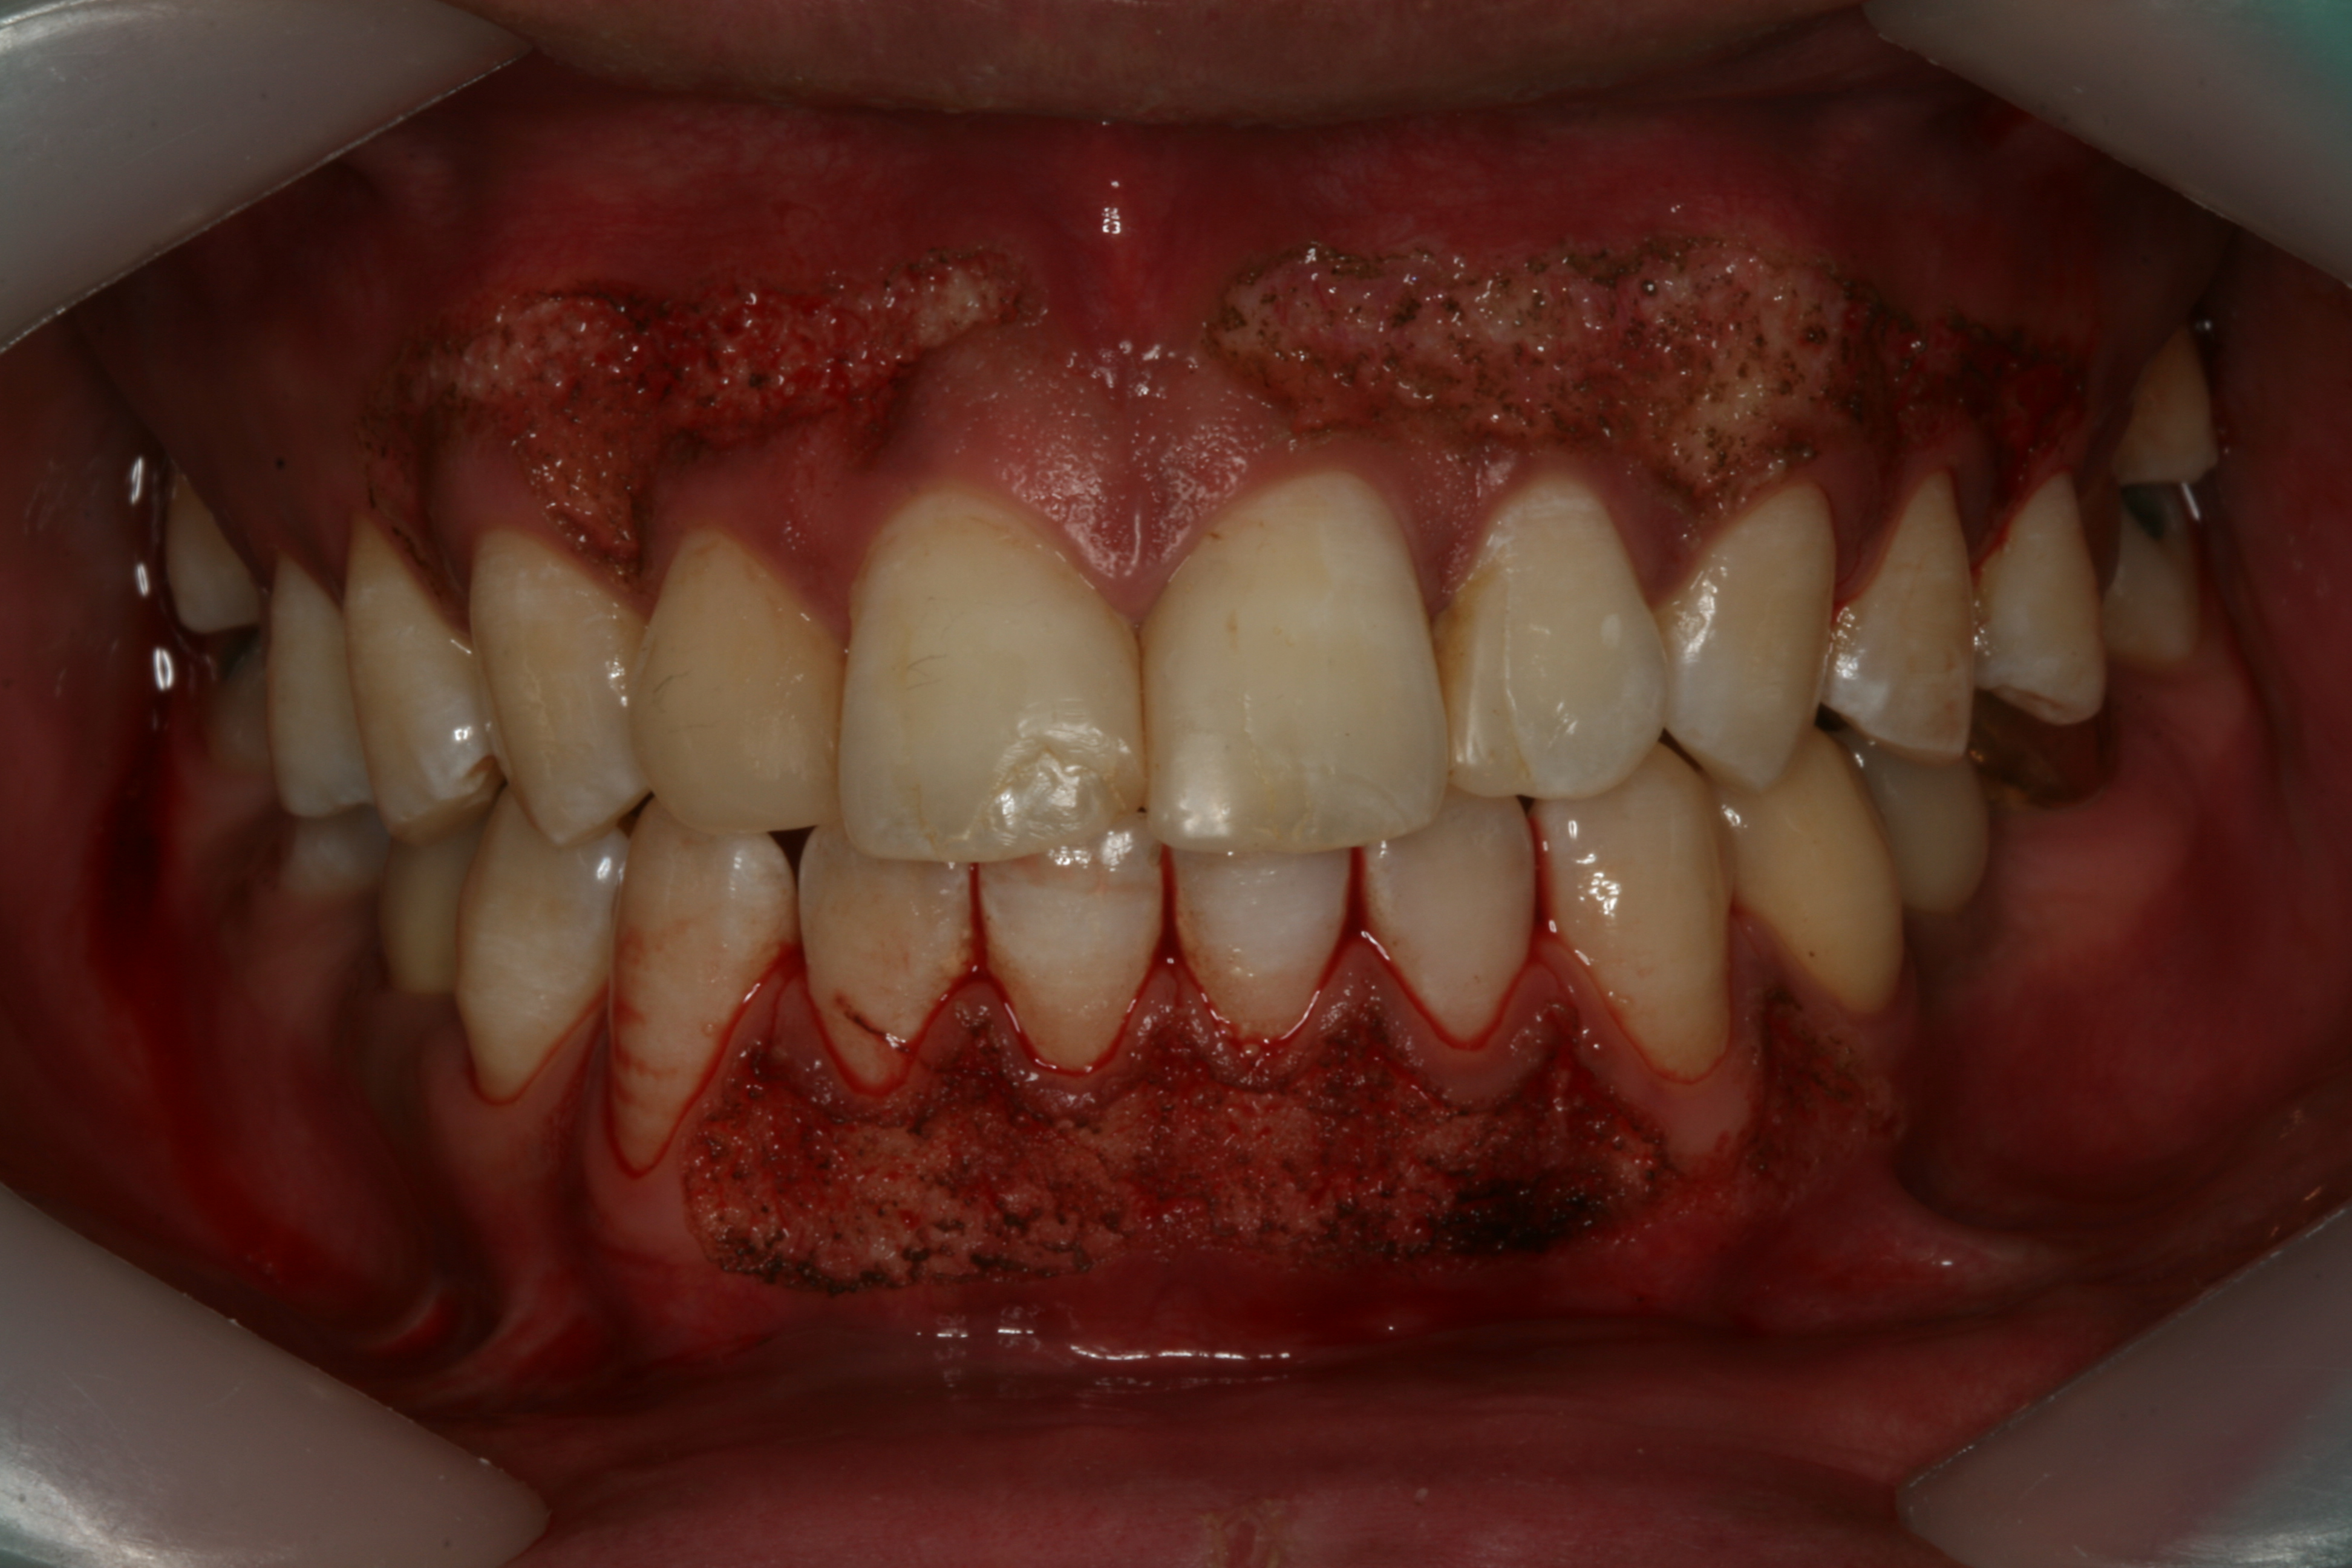

레이저로 멜라닌 색소를 제거한 직후의 모습입니다